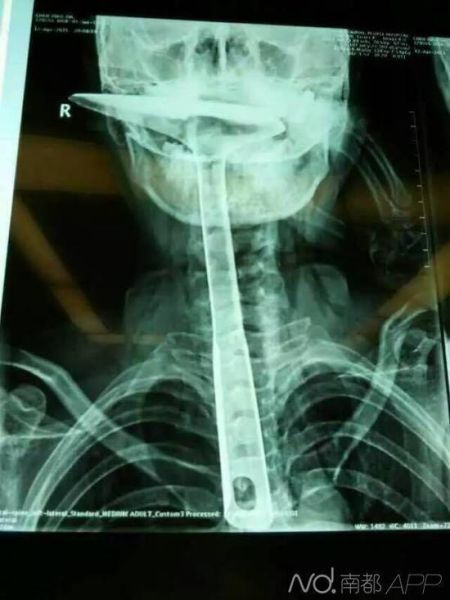

女子因喉咙难受将30公分炒菜锅铲插进食道(图)

炒菜用的锅铲长达30公分,活生生插进自己的食道。南都讯 记者肖佩佩 炒菜用的锅铲,长达30公分,活生生插进自己的食道,只剩下铲勺露在嘴巴外面,整个食道严重受损。医生都不禁感叹:“这真的是50年难遇的病例。”

陈女士被紧急送到东莞第五人民医院,医生拍片显示,整个铁锅铲把手已经在胸里了,病情严重。当晚,陈女士就被转到了康华医院。“患者来院时,嘴巴里只剩一个锅铲铲勺露在外面,整个锅铲手柄已经被插入到食道里了。”康华医院胸外科接诊医生陈羽彪说,检查发现,锅铲总长大概30公分长,手柄直径约2.5公分,整个已经插入食道,食道表皮粘膜损伤严重,且被捅破了一个洞,“而且,手柄已严重挤压到了肺部,导致右肺部已无法正常扩张。”

“这样的病例,不说100年难遇,也是50年难遇了。”康华医院胸外科主任肖朴说,患者情况严重,医院立即组织专家会诊。“胸腔全是大血管,一旦拔出就有可能大出血,危及性命。”当天晚上11点,医生决定为患者进行一期手术即食道扩置手术,“我们先将锅铲从食道里面拔出来,由于胸位食道受损严重,只能切除了。”

医生介绍,食道总长约25公分,患者切除了20公分,切除部分主要集中在胸位段,食道只保留到了颈部,只能露出来进行医学处理,吞咽口水、积液进行人工及时清理更换。”